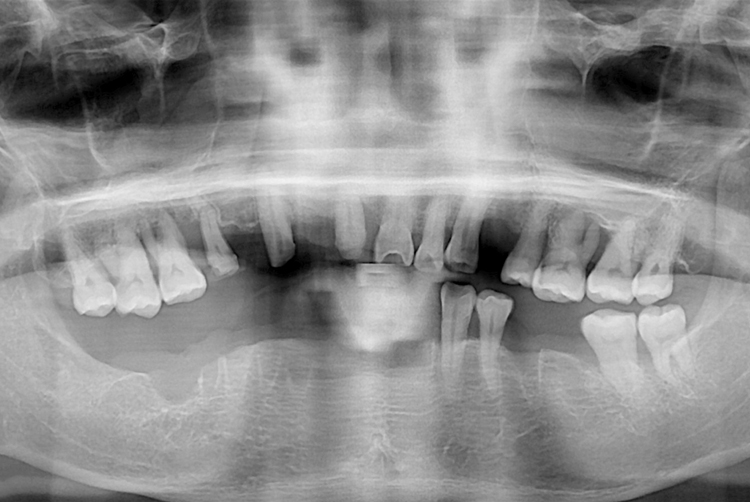

[임플란트] 임플란트

562c18858a7884921cd9c5c25c649e44.jpg

치료전 : 2016-08-27